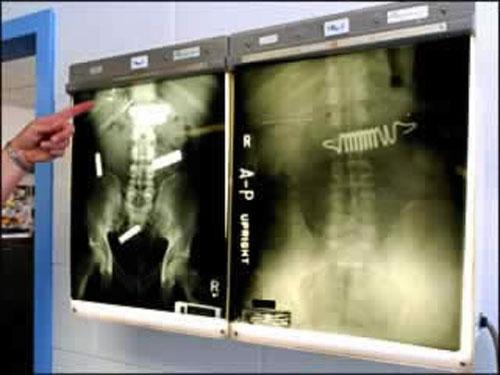

На этом рентгене показан желудок американского мальчика, который глотал магниты…В желудке «плюс» и «минус» соединились, образовав непроходимый «магнитный ком»…

А это рентгены заключённых, которые в надежде попасть в госпиталь глотают кнопки, металлические пружины…